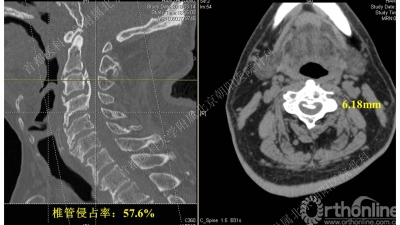

术前CT可见C3-4椎体后缘骨皮质密度条块影,向椎管内隆起,椎管侵占率为57.6%。

CT是诊断后纵韧带骨化的金标准,通过CT矢状位重建有助于辨别骨化块的大小和形状以及椎管狭窄的程度。

有研究表明,当骨化占有率(a/b x 100%)达到30%-60%时很可能发展为颈脊髓病。

MRI用于评估颈脊髓损伤的严重程度以及观察颈脊髓内的病变。